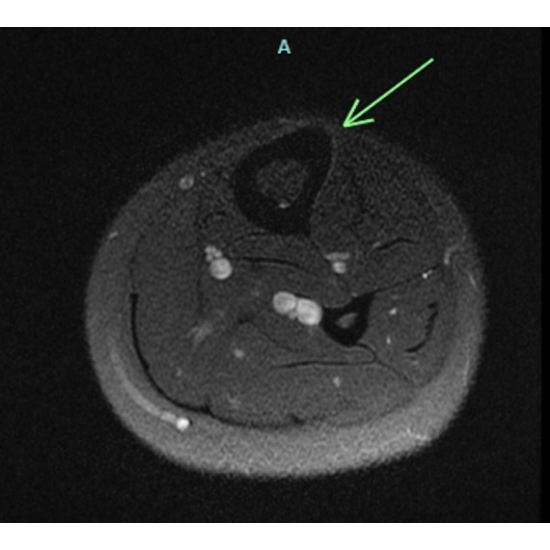

| Hoop Dreams And Bone Nightmares - Page #3 | |||